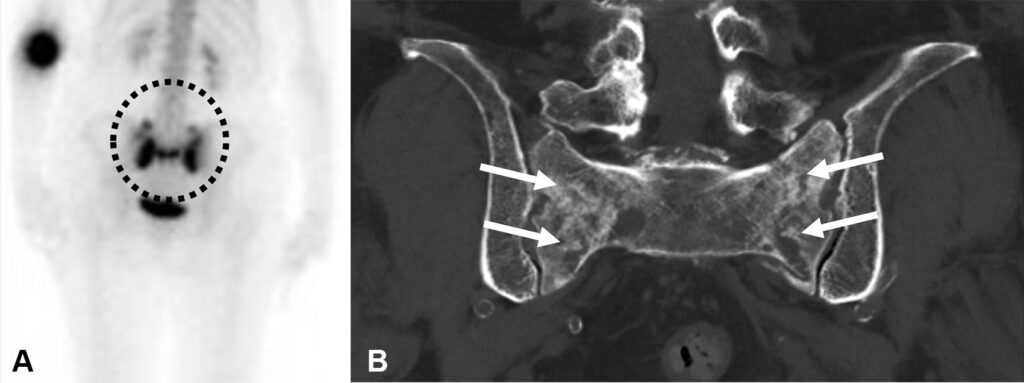

Fratture sacrali da insufficienza in una donna di 82 anni con osteoporosi e lombalgia cronica.

La scintigrafia ossea in proiezione posteriore mirata alla pelvi, evidenzia una netta e simmetrica ipercaptazione a livello dell’osso sacro. Il radiotracciante si distribuisce lungo due bande verticali (corrispondenti alle ali sacrali fratturate) unite da una banda orizzontale trasversale (corrispondente al promontorio sacrale). Questa morfologia ad “H”, che ricorda il logo della nota casa automobilistica, segno di “Honda” (Honda sign) è un segno classico e altamente specifico per questo tipo di lesione.

La TC con ricostruzione coronale conferma visivamente il danno strutturale, mostrando le evidenti rime di frattura verticali a carico del sacro indebolito.

Le fratture da insufficienza si verificano quando uno stress meccanico normale (fisiologico) viene applicato a un osso con resistenza elastica o contenuto minerale ridotti (come nell’osteoporosi grave). Il sacro è una delle sedi più tipiche, e la scintigrafia ossea è estremamente sensibile nell’individuarle anche quando le radiografie tradizionali risultano negative.